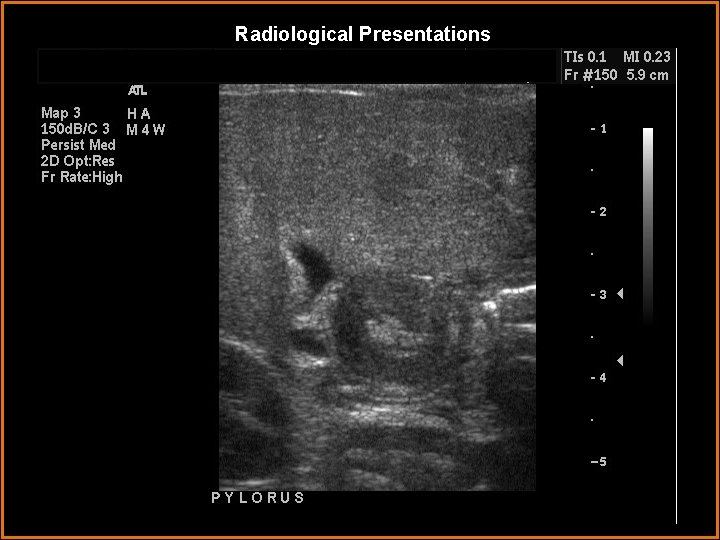

Case History One month old infant with projectile vomiting for three days.

Findings and Differentials Findings: The pyloric muscle thickness is 4. 5 mm and the pyloric channel length is 16. 7 mm. No fluid was observed passing through the pyloric channel, consistent with gastric outlet obstruction. Differentials: • hypertrophic pyloric stenosis. • Pylorospasm.

Diagnosis Hypertrophic Pyloric Stenosis.

Discussion Hypertrophic pyloric stenosis is an acquired condition seen between 2 -8 weeks after birth. Symptoms include projectile vomiting, regurgitation, difficulty in feeding. Bile is usually absent in the vomitus. Prolonged pyloric muscle spasm leading to muscle hypertrophy may be the most important factor in the development of pyloric stenosis. Diagnostic features on ultrasound include: persistent spasm of the pyloric canal with little if any fluid passing into the duodenum, elongation of the pyloric canal more than 1. 2 cm. , persistent thickening of the circular muscle more than 3 mm. The double track sign is noted by ultrasound and is due to sonolucent fluids trapped in compressed mucosal folds. Pylorospasm the most common cause for gastric outlet obstruction in infancy and is multifactorial in etiology. It may be the precursor of pyloric stenosis. However muscular wall is not thickened and, when observed over several minutes peristalsis will pass through the antrum, revealing a pyloric channel of normal length. The obstruction is not fixed, and gastric contents will be observed passing through the pylorus.